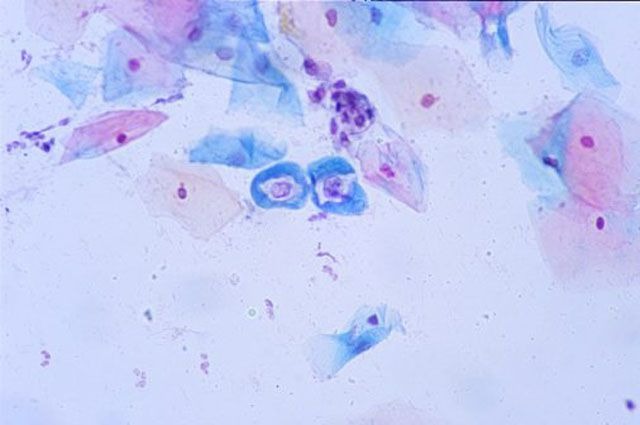

На основании полученных данных судят об удовлетоворительной или неудовлетворительной кольпоскопической картине. Это исследование проводят с использованием специальной окраски по методу Папаниколау, поэтому оно часто встречается под термином PAP test.

Окраска мазка по методу Папаниколау